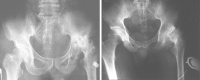

耻骨结核的临床表现

本病常见于育龄妇女,不合并其他部位结核者,多无全身症状,一般发病缓慢,局部疼痛轻微,骨质破坏较重常有跛行。局部常见肿胀,压痛明显,就医时局部多已有脓肿或窦道形成。患侧髋关节除外展略受限外,无功能障碍。